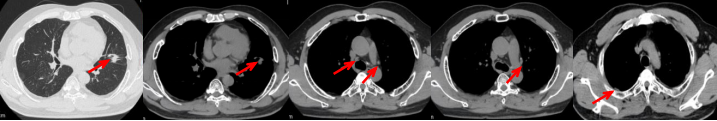

53岁男性,无吸烟饮酒史,脑血栓病史。2024年7月胸部CT:右肺下叶见一团块状软组织密度影,范围约10.8×9.0cm,边界不清,周围并见斑片状磨玻璃密度影,右肺下叶前底段支气管阻塞。纵隔及右肺门见肿大淋巴结影。考虑右肺下叶支气管肺癌。伴纵隔及右肺门淋巴结转移瘤,右下肺静脉瘤栓。2024.7.23行肺穿刺取病理:(肺)腺癌伴有神经内分泌分化。NGS基因检测:RET KIF5B exon15-RET exon12融合。PD-L1(克隆号28-8)TPS=90%。

治疗经过:2024.08开始口服赛普替尼(160mg,bid)。2024.09复查胸CT评效PR。2025.1复查胸CT:右肺下叶外基底段见一不规则形实性肿块,大小约94mm×87mm,边缘呈分叶状,其内密度不匀。右侧胸腔见少许水样密度影。评效PD,PFS=5个月。患者未同意再次组织活检,目前应用卡博替尼治疗,仍在随访中。治疗期间未出现毒性反应。

55岁男性,无吸烟史,有饮酒嗜好。2024年11月常规体检胸CT:左肺上叶占位性病变,大小约2.7×2.4cm,恶性可能大;左肺、左侧叶间胸膜及胸膜下多发微小结节,转移待除外。左侧胸腔积液,部分骨质改变。2024年12月初肺穿刺活检,病理:(肺)腺癌。NGS基因检测:CCDC6-RET(exon1-exon12)融合突变阳性(丰度:13.21%)。PD-L1表达阳性(TPS=35%,CPS=45)。

治疗经过:2025.01开始口服普拉替尼(400mg,qd)。2025.03复查胸CT:左肺上叶、右肺上叶、左肺斜裂见多发实性结节影,长径范围约3-17mm,较大者大小约17mm×12mm,位于左肺上叶下舌段,可见分叶、毛刺、胸膜凹陷、棘状突起征象。纵隔内小淋巴结。评效PR,随访中。治疗期间未出现毒性反应。